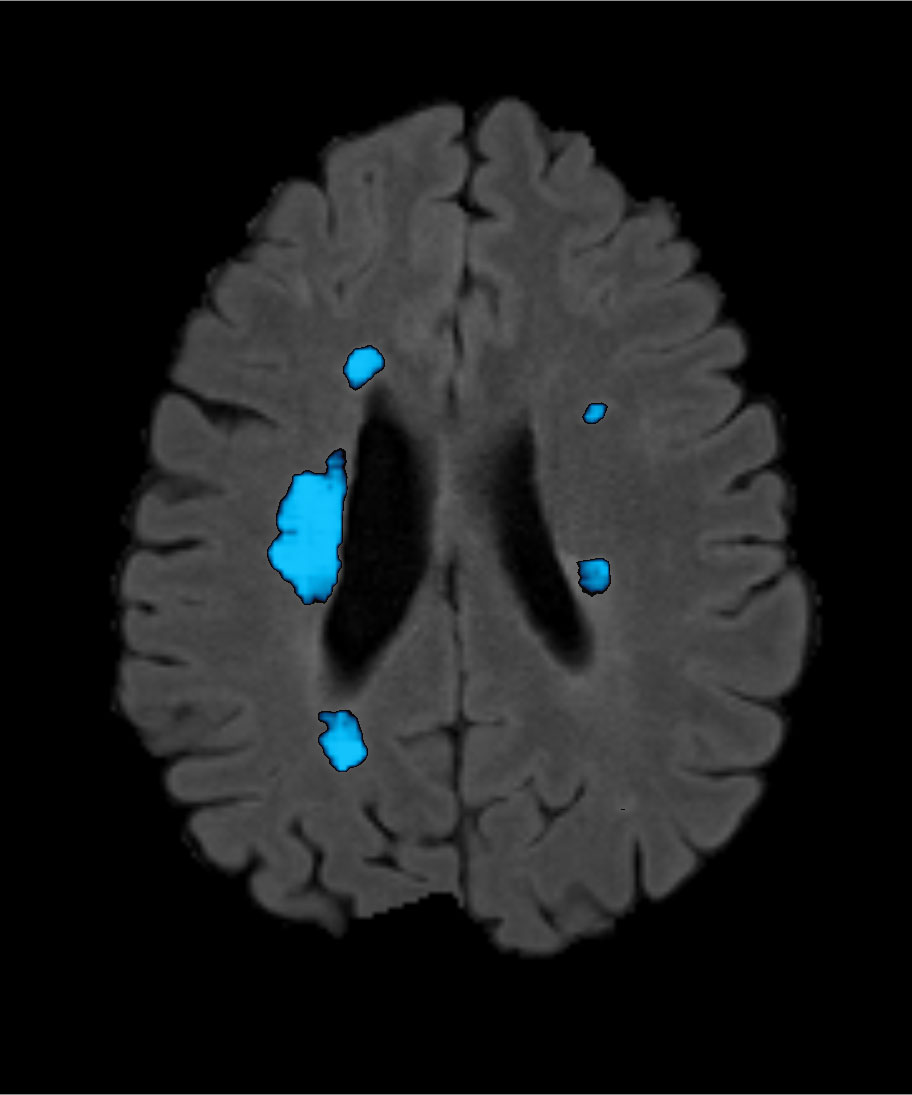

AI:ON Multiple Sclerosis

AI:ON’s artificial intelligence technology effectively segments MS lesions in brain MRI scans for comprehensive review by radiologists.